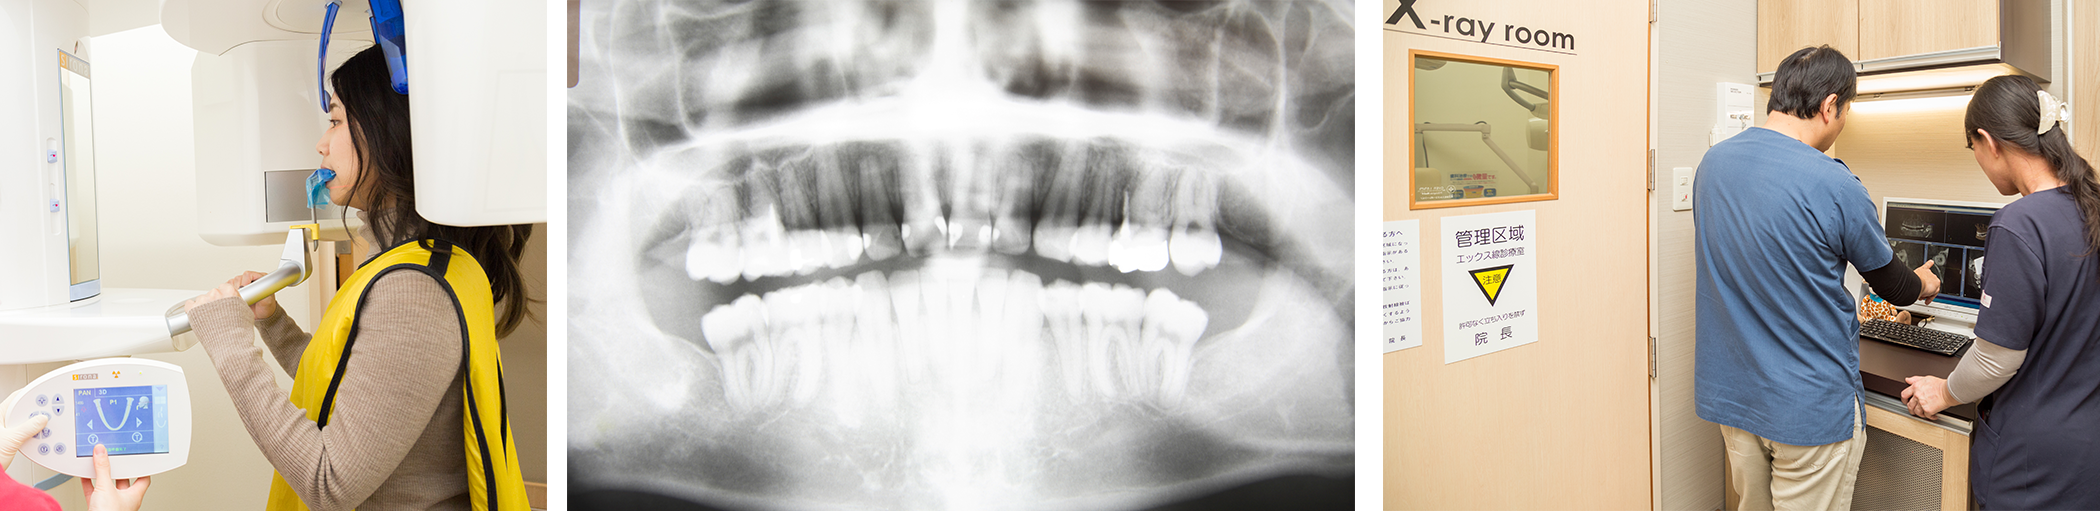

正確な診断、安全な治療を行うための先進設備

パノラマレントゲン、歯科用CT

歯科用のCTは頭頸部に特化したX線装置で、3次元の立体的な情報を得ることができるので、歯科の診断に大きな役割を果たします。

従来のX線では見ることのできなかった歯と顎の骨の大きさや位置関係がわかり、インプラントや矯正治療の安全性や確実性の向上に欠かせません。